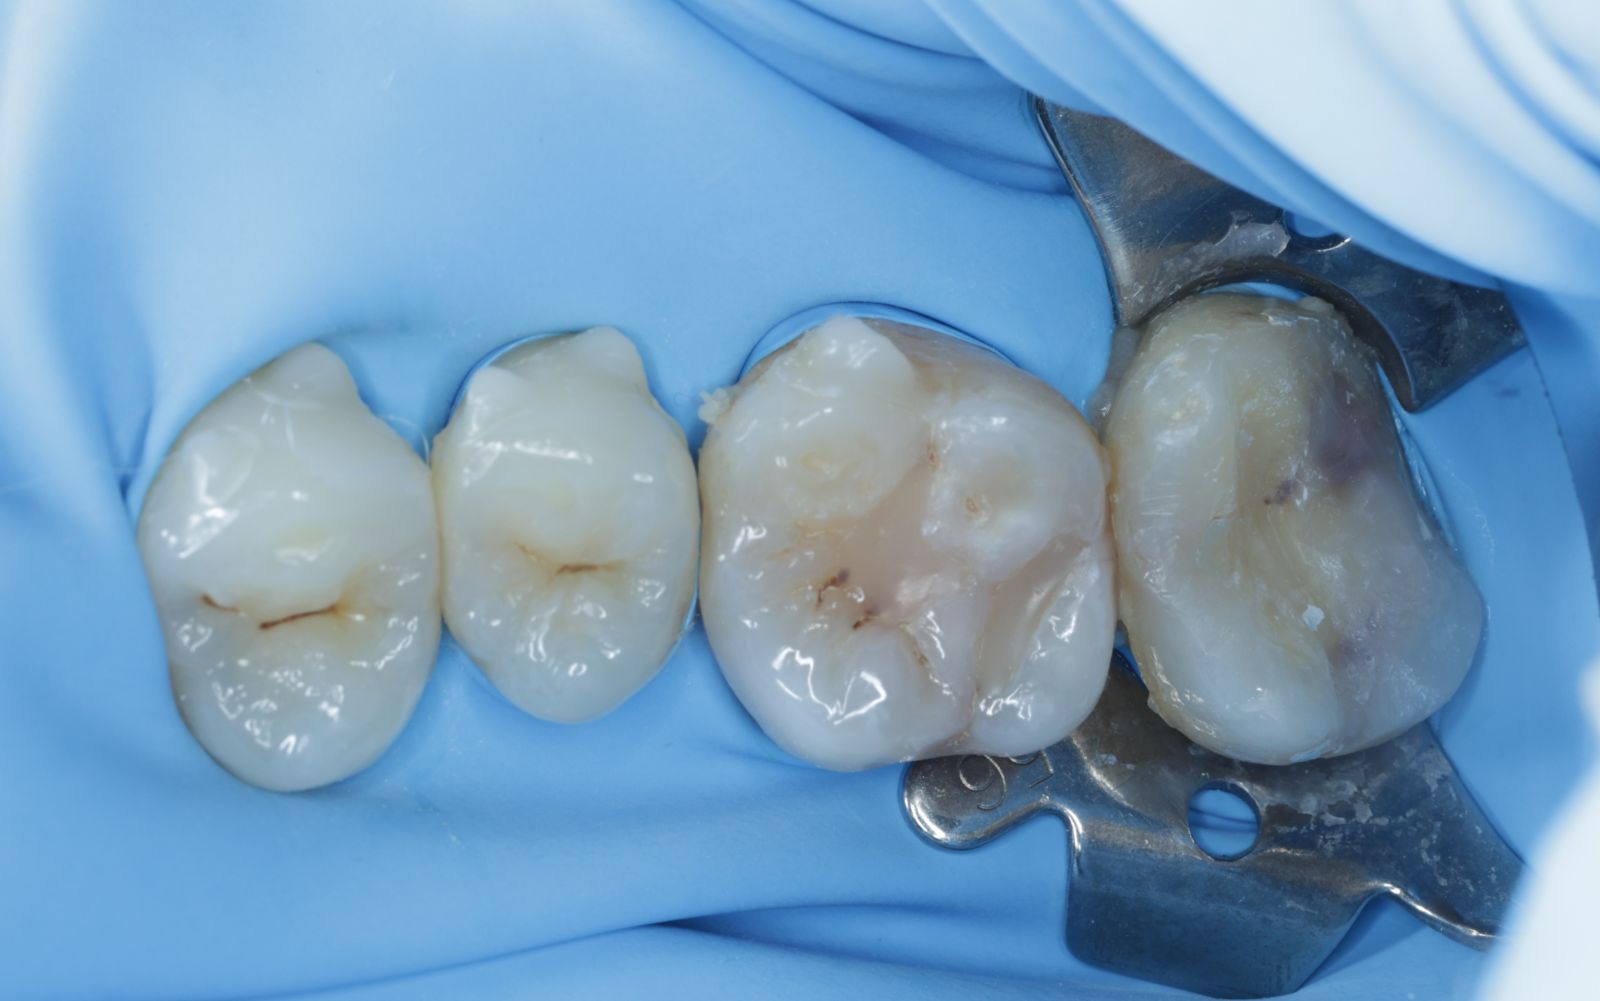

【 案 例 三】

- 有時候表面上看起來是蛀牙是一個小缺口,其實裡面已經是範圍很大的蛀牙了!用隔濕的小帳棚隔絕汙染、清理蛀牙,缺損的齒質就靠陶瓷齒雕(瓷塊)做修復!仿真的色澤及外觀,讓你看不出來牙齒曾經的損傷。